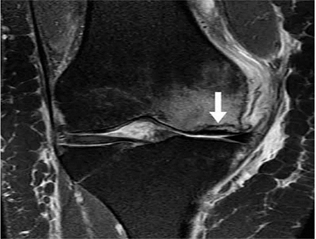

Hình 3. Hình ảnh cộng hưởng từ có trọng số mật độ proton sagital có sụn chêm bên dạng đĩa với tín hiệu tăng trong sụn.

Chiều dài trung bình của sụn từ bờ trong ra ngoại vi xấp xỉ 11-12 mm [2]. Sụn dạng đĩa hoặc sụn không hoàn toàn xảy ra khi chiều dài sụn vượt quá 14 mm [3], do mô sụn kéo dài ra xa hơn về trung tâm để bao phủ nhiều bề mặt khớp mâm chày hơn. Hình ảnh sagittal tuần tự cũng có thể gợi ý mặt sụn dạng đĩa nếu mặt sụn duy trì hình dạng hình chữ nhật hoặc hình nơ trên nhiều hơn hai hình ảnh sagittal liên tiếp, nếu độ dày lát cắt từ 4 mm trở lên (dấu hiệu “thắt nơ”). Các sụn đĩa đệm bên phổ biến hơn nhiều so với các hình tượng sụn ở giữa.